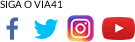

O tomógrafo, adquirido com investimento superior a R$ 3 milhões, viabilizado com o apoio do Governo do Estado da Bahia, foi instalado em ambiente próprio e tecnicamente adequado. O equipamento permite diagnósticos mais rápidos e precisos, fundamentais especialmente em casos de urgência e emergência.

A ampliação da Enfermaria clínica cirúrgica melhora a distribuição de leitos e qualifica o acompanhamento de pacientes no pré e pós-operatório. Já a nova sala de medicação otimiza procedimentos, organiza protocolos e garante mais eficiência às equipes de saúde, oferecendo ainda mais conforto em um ambiente estruturado e de alto padrão.